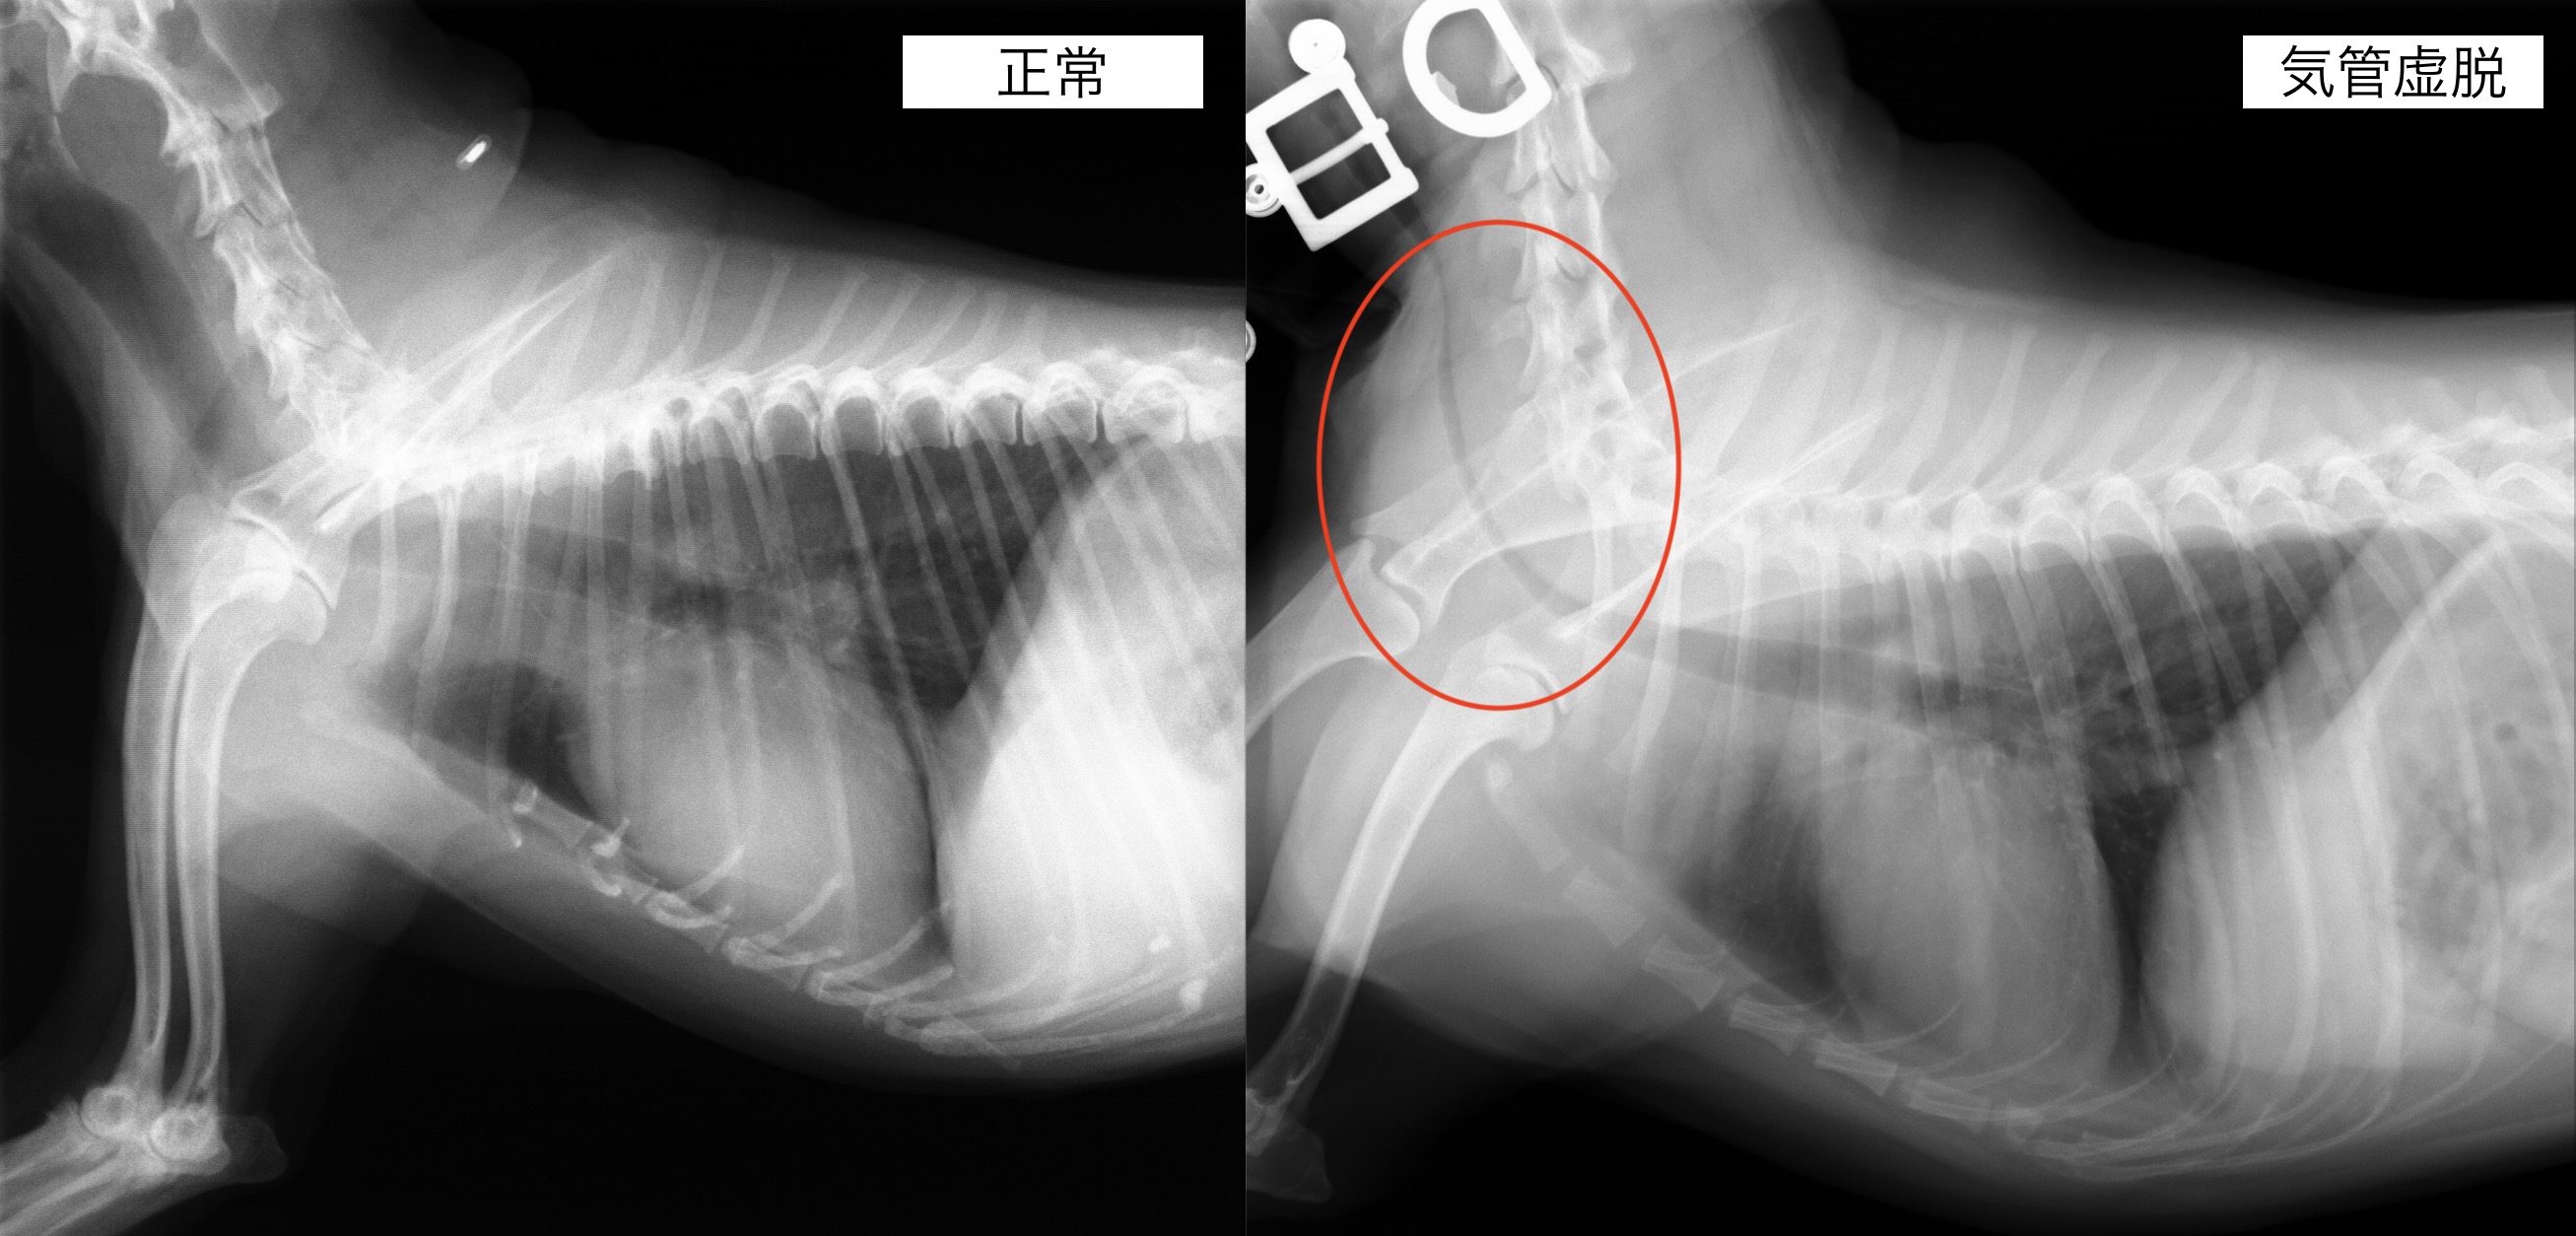

気管虚脱の犬の1例(咳、ガチョウのような呼吸、気管)

犬の気管虚脱は原因不明の気管の扁平化が原因となる呼吸障害です。

レントゲン検査では、吸気時の期気管が閉塞している所見が認められました。